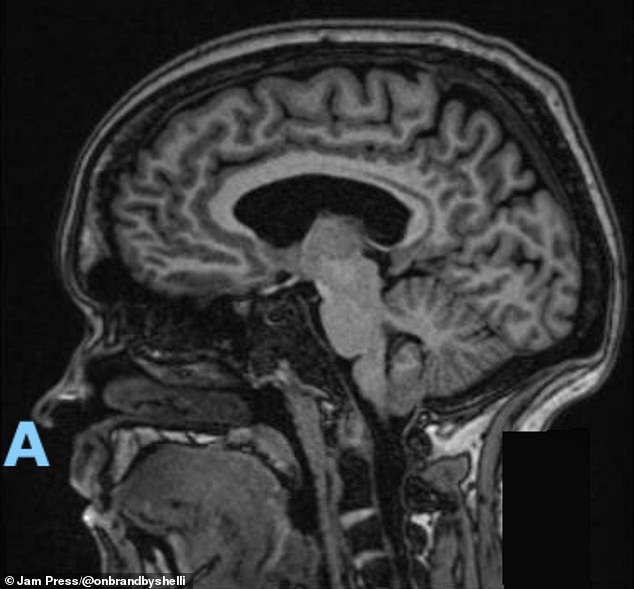

That crisis finally led to a neurology referral and the MRI that revealed a 4mm Chiari malformation. Even then, doctors initially said surgery wasn’t needed. But Gunnoe’s symptoms kept worsening, as simple movements like bending or standing provoked dizziness or instability.

That crisis finally led to a neurology referral and the MRI that revealed a 4mm Chiari malformation, pictured here

Chiari malformation, which is a rare condition impacting around 300,000 Americans, causes the lower part of the brain to push down into the spinal canal

A neurologist used a skull model to show how her cerebellar tonsils were being pulled downward into the opening at the base of her skull.

‘He explained that mine are pushed down further than they should be, slipping through the opening where the spinal cord runs,’ she said.

‘Because they’re squeezed into a space that’s too tight, they press on my spinal cord and disrupt the flow of cerebrospinal fluid.’

When that flow is slowed or blocked, she added, ‘it irritates the nerves and causes many of the symptoms I’ve been dealing with.’